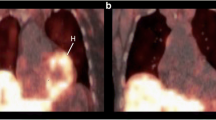

We recently investigated the suitability of 11C-donepezil to image parasympathetic denervation in 12 early-to-moderate stage PD patients and 12 healthy controls [63•]. The PD patients displayed a highly significant 35 % decrease in small-intestine signal, which was visually apparent in most individual patients (Fig. 2). Decreased signal in the pancreas was also seen in the majority of patients. No correlations were seen between the PET signal and disease duration, gastric emptying time, or severity of constipation.

11C-donepezil PET images. a Whole body PET scan of a healthy, male subject. b Summed PET images (55–60 min post-injection) of the upper abdominal region in a healthy control (top) and a PD patient (bottom). Note the visually apparent decrease in the small-intestine signal. l liver, p pancreas, s small intestine